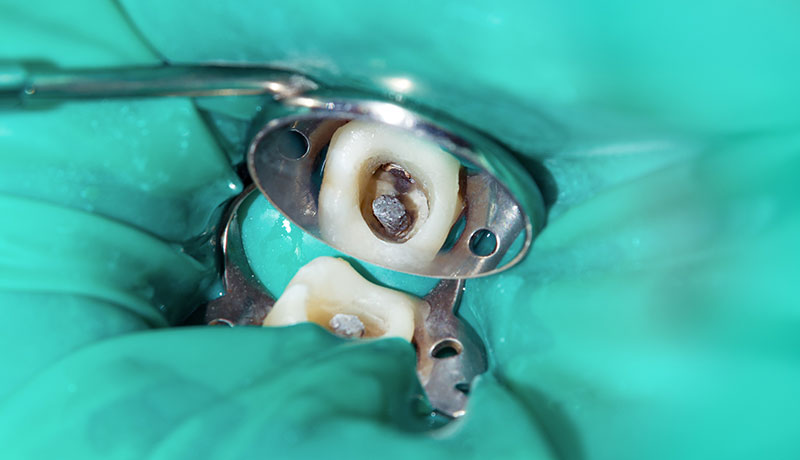

根管治療(歯の根の治療)

根管治療とは、虫歯が重度に進行し、歯の神経に炎症や感染が及んだ際に行う治療です。

感染した神経を除去し、根管内を洗浄、消毒することで、歯を残し、将来的な抜歯を回避することを目指します。根管治療では高い精密性が求められるため、当院ではラバーダムなど、再感染を防ぐための機器を使用し、治療成功率を高めております。